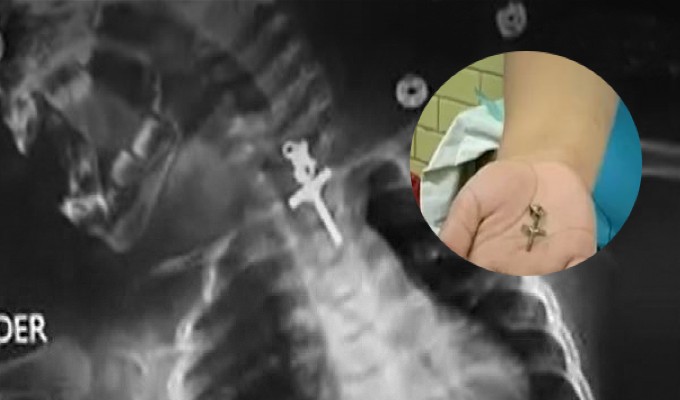

Los médicos identificaron el artículo luego de realizarle un examen de tórax a la menor.

Los médicos identificaron el artículo luego de realizarle un examen de tórax a la menor. Los especialistas de Essalud actuaron de inmediato y le practicaron una endoscopia terapéutica para extraer el objeto de manera exitosa.

Pese a que se trató de una intervención complicada, ya que el crucifijo estaba incrustado y había una alta probabilidad de causarle severos daños a la menor, pero el procedimiento tuvo buenos resultados, indicaron los médicos.